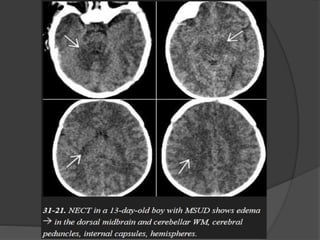

Maple Syrup UrineDisease Symptoms usually develop within a few days after birth and include poor feeding, lethargy, vomiting, and seizures. In severe cases, the urine smells like maple syrup or burnt sugar. NECT scans show profound hypodensity in the myelinated WM with vasogenic edema in the (Areas of early myelination) dorsal brainstem, cerebellum, cerebral peduncles, and posterior limb of the internal capsule. MR scans show striking T2/FLAIR hyperintensity with relatively crisp margins. DWI shows restricted diffusivity